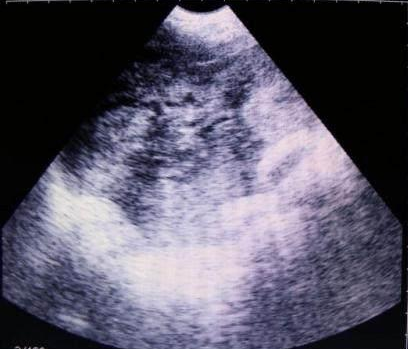

獸用B超機(jī)檢測(cè)母豬空懷圖像